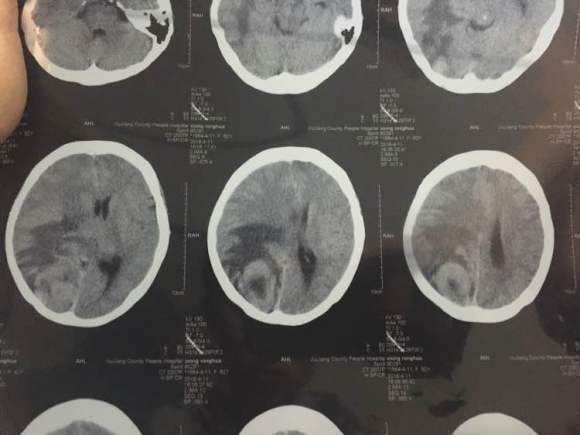

一个人旅行,牵挂的心 02021-10-15 患者家属我婆婆两年前查出肺癌早期,切除两片肺叶,一个月前出现头疼,昨天拍了片子,医生说情况不太好,我这里三四线城市,现在劝她...